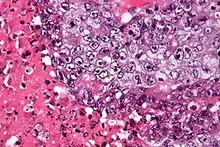

| Micrograph of an embryonal carcinoma showing its typical features – prominent nucleoli, marked nuclear atypia, necrosis, and nuclear overlap. H&E stain. | |

The gross examination usually shows a two to three centimetre pale grey, poorly defined tumour with associated haemorrhage and necrosis.[2]

The microscopic features include: indistinct cell borders, mitoses, a variable architecture (tubulopapillary, glandular, solid, embryoid bodies – ball of cells surrounded by empty space on three sides), nuclear overlap, and necrosis.

An important key to distinguish it from other tumors, such as seminoma (vacuolated), teratocarcinoma (three differentiated germ layers), yolk sac tumor (Schiller–Duval bodies), and the Sertoli–Leydig cell tumor (strings of glands), is that the embryonal carcinoma cells are "trying" to evolve into their next stage of development. So in the testicle, they are often observed as blue cells attempting to form primitive tubules.[5]